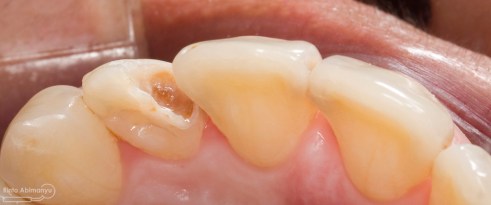

Kasus hari ini ceritanya datang seorang pasien wanita usia sekitar 50 an mengeluhkan gigi2 atas kirinya sering terselip makanan dan terkadang terasa senut-senut…

Pada pemeriksaan intra oral terlihat gigi 23 dan 24 mengalami karies dan cukup banyak sisa makanan terjebak disana…

Pemeriksaan respon dingin pun menunjukkan hasil negatif, untuk menambah data dalam penegakan diagnosis maka dilakukan pengambilan ronsen pada gigi2 tersebut

Terlihat dari ronsen tersebut karies pada gigi 23 24 sudah mencapai pulpa… dari informasi pemeriksaan klinis dan ronsen maka didiagnosis gigi tersebut nekrosis.. Saya jelaskan kepada pasien mengenai kondisi gigi2 nya dan rencana perawatan yang akan saya lakukan…